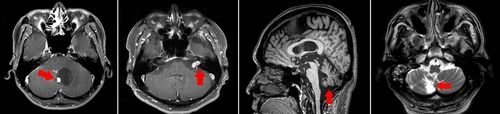

[로이슈 이재승 기자] 올해 28세인 취업준비생 A씨는 두 달 전부터 어지럼증을 겪기 시작했다. 책상에서 갑자기 일어나거나 고개를 휙 돌리면 어지럼증이 더욱 심해졌다. 처음에는 취업 스트레스로 인한 것이라고 생각해 대수롭지 않게 넘겼지만, 토익 시험을 볼 때조차 지문에 집중하기 힘들어지자 심각성을 느껴 가까운 병원을 찾았다. 병원에서 이석증이라는 진단을 받아 약물을 꾸준히 복용했지만 전혀 호전이 없었고 최근에는 증상이 더 심해져, 어두운 곳에 가거나 밤거리를 걸을 때면 휘청거리고 균형을 잡을 수 없어 친구들의 부축을 받아야 했다. 주변 권유로 모 대학병원을 찾은 A씨는 MRI 검사 결과 소뇌종양을 진단받고 큰 충격을 받았다.

뇌종양이 있는 경우에도 종양이 서서히 자라면서 어지럼증과 두통을 느끼게 된다. 주로 50대에서 60대에서 많이 발병하긴 하지만 최근에는 젊은 층의 유병율도 높아지는 추세라 안심할 수 없다. 뇌졸중의 경우 고혈압이나 당뇨가 있는 사람에게서 주로 발생하는데 반해 뇌종양은 뚜렷한 원인 및 예방책이 없어 더 무서운 질환이다. 어지럼증과 함께 종양 위치에 따라 말이 어눌해지는 등 언어장애가 나타나거나 엉뚱한 행동을 하기도 한다.